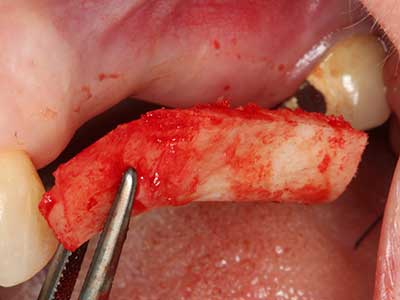

Fig. 3: Basal separation of the block is easier with specially angled attachments.

Fig. 4: Additional autologous bone chips are harvested with the bone scaler.

Fig. 5: Checking the block size at the recipient site.